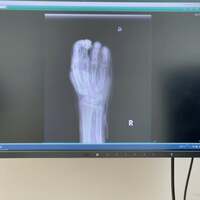

歌手の小柳ルミ子が15日に自身のアメブロを更新。骨折した右手小指の経過観察の結果を明かした。

この日、小柳は「整形外科の経過観察です」と経過観察のために病院を訪れたことを明かし、医師からは「許容範囲ですね」と言われたことを報告。「良いですね…ではなく許容範囲か」と肩を落とした様子で述べ「骨折した箇所を抑える為にパッチを当ててた所がこんなになってました」と写真とともに説明した。

続けて「折れてる所を抑えて指を動かす…のです」「エコー見ながら」と診察中の様子を明かし「痛い やっぱり骨折してんだ~」とコメント。「パッチを患部に直接当たらない様にこれを貼って下さいました」と写真とともに説明し「ギブスはめる時も痛いのよね~」(原文ママ)とつづった。